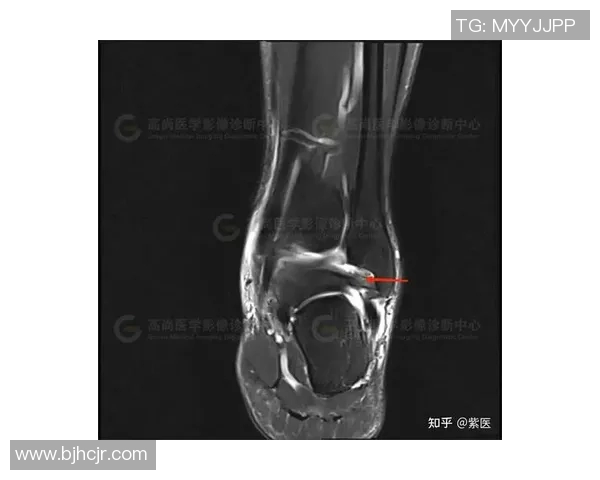

医生通常会通过物理检查以及影像学检查(如X光或MRI)来确认是否存在韧带撕裂。在明确诊断后,可以制定相应治疗计划,以确保患者能够得到最佳康复效果。